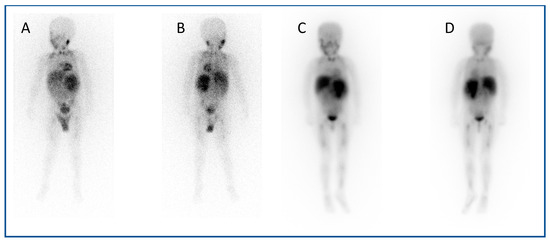

A similar approach is used with serial 111In-labelled anti-CD66 monoclonal antibody SPECT (single photon emission computed tomography) CT imaging (Figure 4) for dosimetry prior to 90Y anti-CD66 monoclonal antibody therapy, as an alternative to total body irradiation as conditioning prior to allogeneic bone marrow transplantation for relapsed leukaemia, to ensure that organ at risk doses are not exceeded [50].

Figure 4.

Dosimetry imaging with 111In-labelled anti-CD66 monoclonal antibody in a patient with relapsed leukaemia prior to 90Y anti-CD66 monoclonal therapy in an early phase trial [50]. (A) Anterior and (B) posterior whole-body planar scintigraphy views; (C) axial, (D) coronal and (E) sagittal fused SPECT CT views; and (F) SPECT maximum intensity projection image. These demonstrate avid uptake in areas of involved bone marrow.